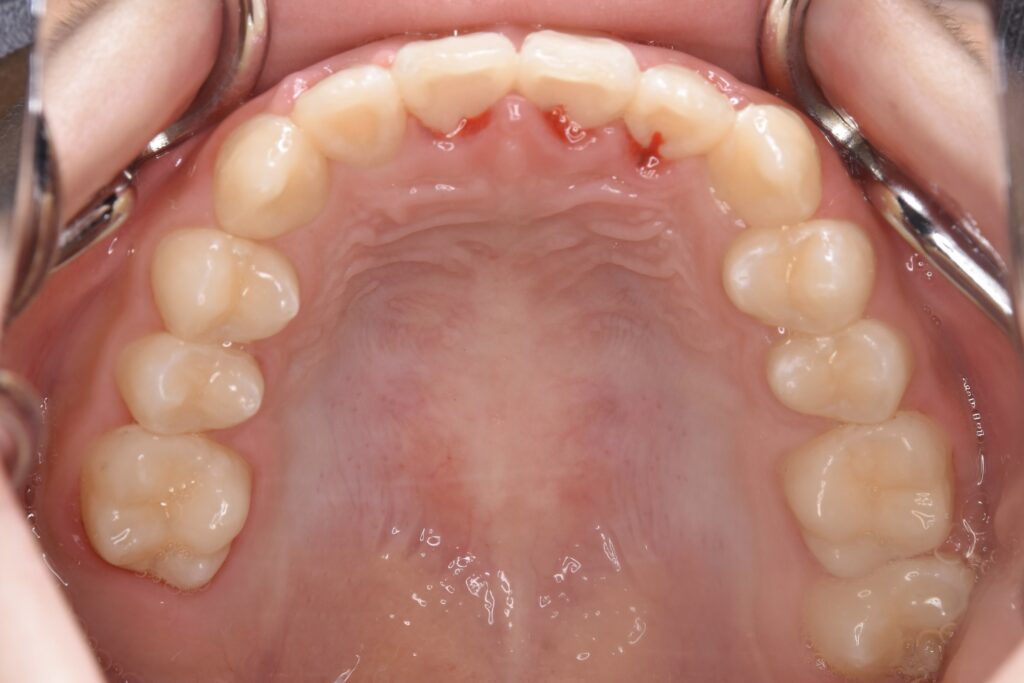

7歳 男児 小児矯正

BEFORE

主訴 通っている歯医者で矯正した方がいいと言われて気になっている。下の前歯がでこぼこしている。

診断名・主な症状 下顎前歯の叢生を伴う過蓋咬合

治療内容 上下の歯並びの幅を拡げつつ、前歯の関係を改善しました。

使用装置 急速拡大装置

リンガルアーチ

機能的矯正装置(マイオブレース)

抜歯部位 抜歯なし

治療期間 2年 + 後戻り止め期間(3年 )

通院回数 20回

費用 50万円程度(税別)  29331

リスク・副作用 痛み、歯肉退縮、歯根吸収、抜歯に伴う出血や腫れが生じることがあります。